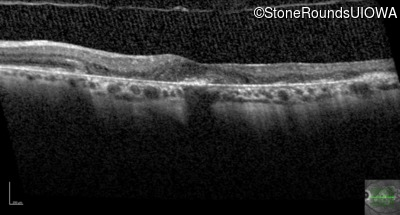

Optical Coherence Tomography - Right - 20/25

Exemplar / OCT Stack

Optical Coherence Tomography - Left - 20/25 -2